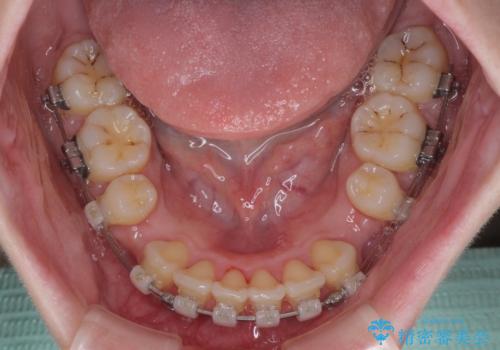

- 矯正装置

- クリアブラケット

- 1年10ヶ月

来院された時から4本の抜歯が必要であることを理解されていらしており、通法通り上下左右の第一小臼歯4本を抜歯し、ワイヤー装置にて矯正治療を行うこととしました。